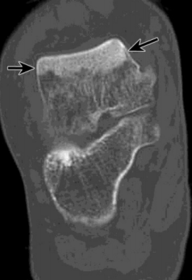

| What is this? | Posterior talocalcaneal coalition |